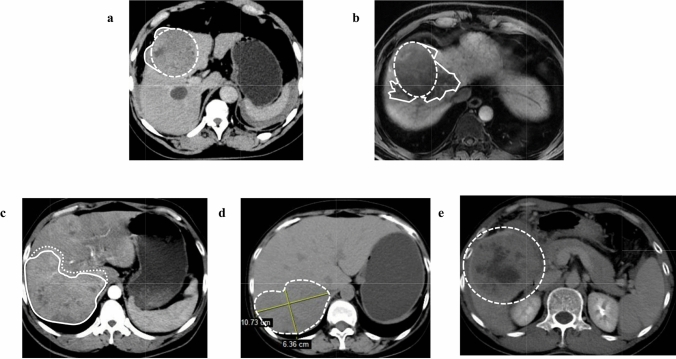

Background: Immune checkpoint inhibitors (ICIs) are playing a significant role in the treatment of hepatocellular carcinoma (HCC). This study aims to explore the prognostic value of alpha-fetoprotein (AFP) and initial tumor shape irregularity in patients treated with ICIs.

Methods: In this retrospective, multi-center study, 296 HCC patients were randomly divided into the training set and the validation set in a 3:2 ratio. The training set was used to evaluate prognostic factors and to develop an easily applicable ATSI (AFP and Tumor Shape Irregularity) score, which was verified in the validation set.

Results: The ATSI score was developed from two independent prognostic risk factors: baseline AFP ≥ 400 ng/ml (HR 1.73, 95% CI 1.01-2.96, P = 0.046) and initial tumor shape irregularity (HR 1.94, 95% CI 1.03-3.65, P = 0.041). The median overall survival (OS) was not reached (95% CI 28.20-NA) in patients who met no criteria (0 points), 25.8 months (95% CI 14.17-NA) in patients who met one criterion (1 point), and 17.03 months (95% CI 11.73-23.83) in patients who met two criteria (2 points) (P = 0.001). The median progression-free survival (PFS) was 10.83 months (95% CI 9.27-14.33) for 0 points, 8.03 months (95% CI 6.77-10.57) for 1 point, and 5.03 months (95% CI 3.83-9.67) for 2 points (P < 0.001). The validation set effectively verified these results (median OS, 37.43/24.27/14.03 months for 0/1/2 points, P = 0.028; median PFS, 13.93/8.30/4.90 months for 0/1/2 points, P < 0.001).

Conclusions: The ATSI score can effectively predict prognosis in HCC patients receiving ICIs.